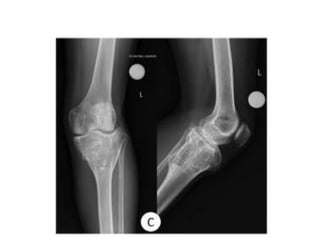

1 year later

AUG 2010

• 42.

• 43.

• 44.

• 45.

• 46.

• 47.